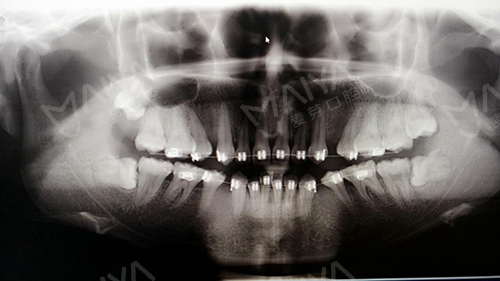

何小姐牙齿全景片

经过口腔全景片检查,张超主任全面分析认为何小姐可继续使用托槽矫正,不拆卸,同时为何小姐量身制定了分阶段的矫正方案,第一步减轻压力,让牙齿慢慢恢复正常状态;第二步细丝轻力让牙齿缓慢移动让骨改建再平衡,第三步排列牙齿内收关闭拔牙间隙,改善牙齿前突,此方案在既不改善脸型的同时又减轻了痛苦。